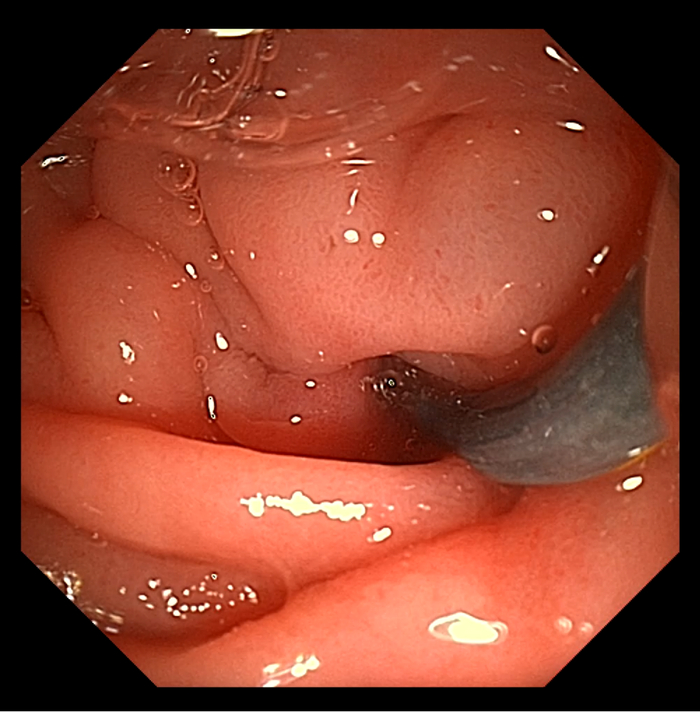

患者男,56岁,十二指肠镜提示慢性胰腺炎,CT下显示胰管结石。

CT下可见,结石狭窄处

导丝已插入胰管(右上

由此病例可见,即使是面对高难度的双导丝技术胰管内取石,澳华全新UHD系列十二指肠镜仍然可以凭借良好的操控性能,让医者诊疗时十分得心应手。且在更大的抬钳器角度的匠心设计下,医生可以更轻松、准确地插入耗材,大幅缩短手术时间。